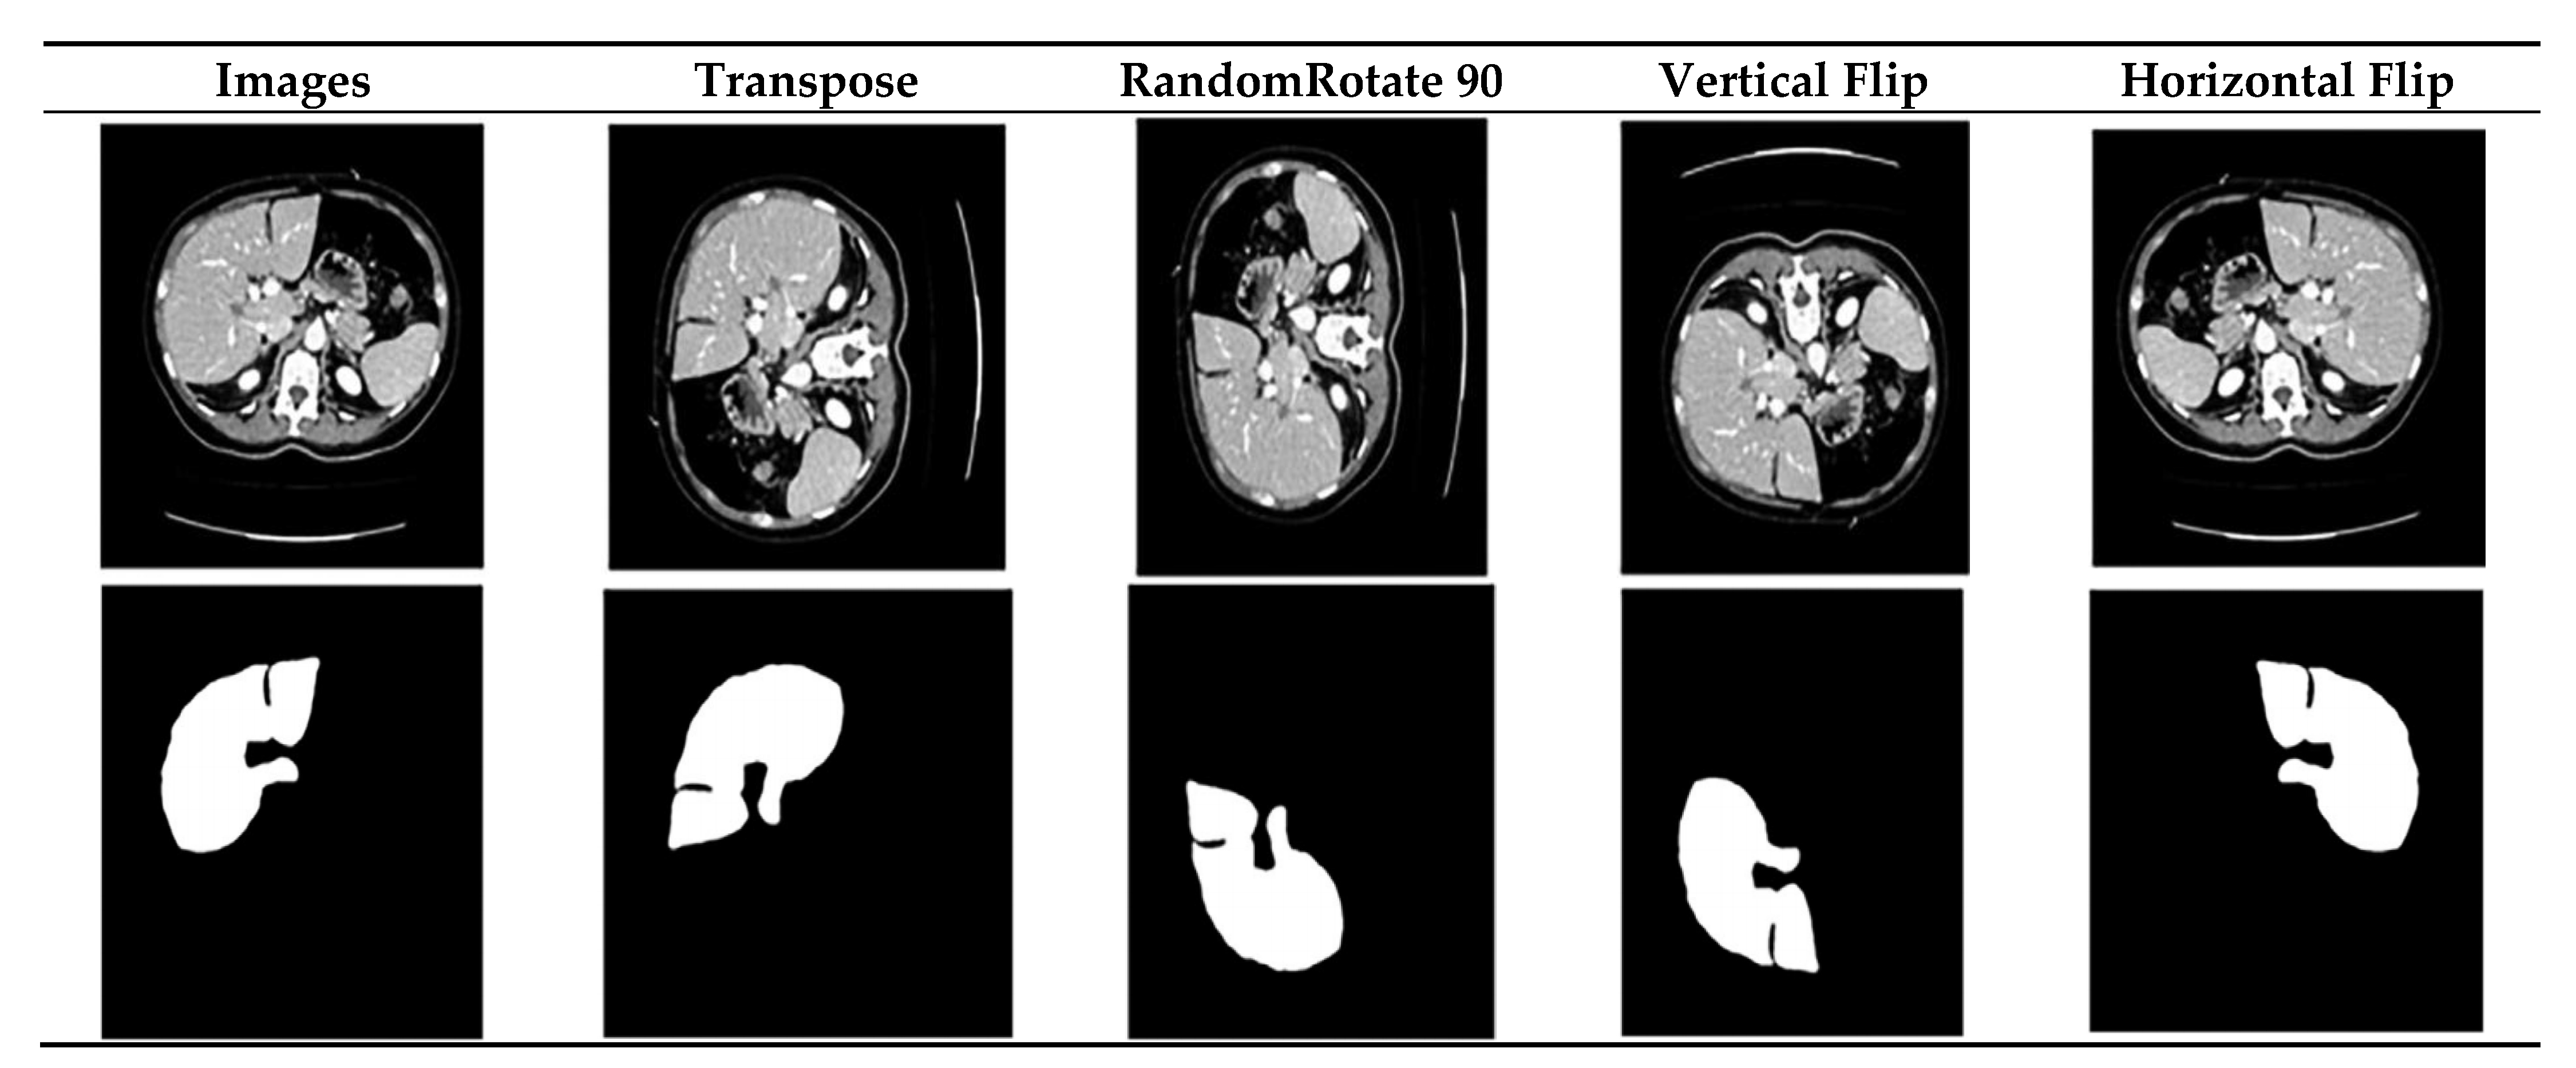

3.2. Data Augmentation